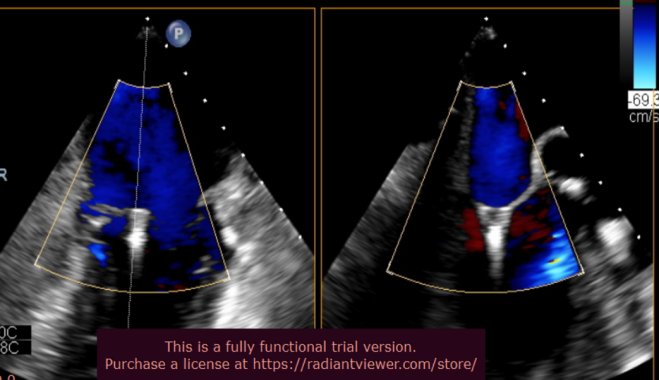

手术于全麻下进行,术前TEE提示重度功能性二尖瓣反流,反流位于A2/P2,瓣膜活动度可(图1)。手术采用经典股静脉房间隔途径,房间隔穿刺后置入24F导引导管及二尖瓣夹输送系统,在TEE引导下准确植入一枚二尖瓣夹,瓣膜夹位置稳定,植入后反流基本消失(图2),二尖瓣跨瓣平均压力阶差2mmHg,双孔化形成,遂移除器械输送系统。患者术后恢复良好,瓣膜夹位置稳定,拟于近期出院。

图1:术前TEE提示二尖瓣重度反流,反流位置位于A2/P2区